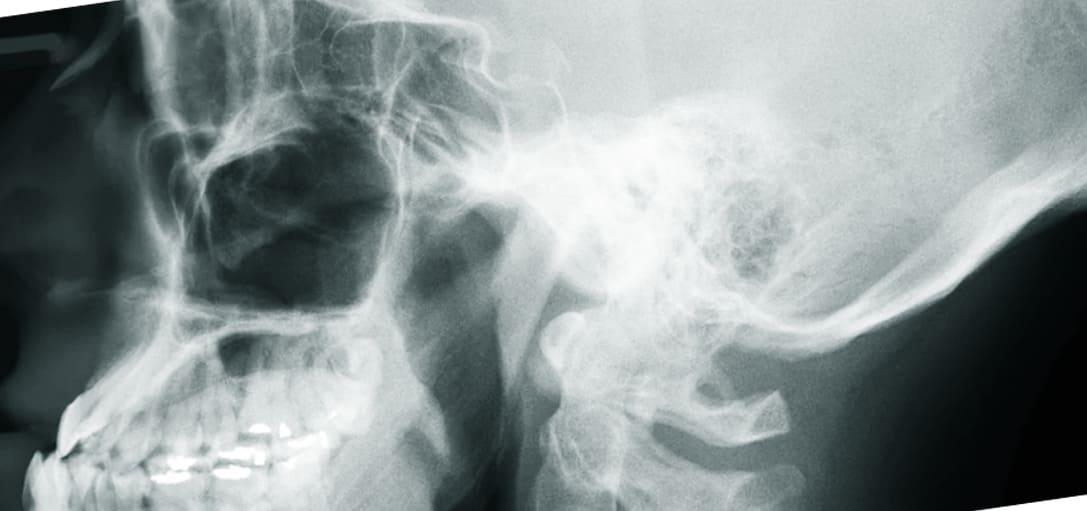

예를 들어 빠진 이빨 옆에 있는 정상 치아들이 조금씩 움직이거나 부식되면서 부정교합이 올 수도 있습니다. 심지어는 안면 비대칭 등과 같은 문제로도 이어질 수 있는 만큼 조속한 치료 혹은 임플란트를 해야 합니다.

어금니 임플란트를 생각하면 빠진 곳에 새로운 이를 심는다라고 생각할 텐데요. 하지만 치과 입장에서는 그리 간단한 시술이 아닙니다. 생각보다 난이도가 있는 수술이기 때문에 비용이 높게 책정되는 것인데요.

가장 중요한 것은 현재 자신의 구강 상태가 어떤지가 핵심입니다. 단순히 어금니 임플란트만 이식하면 되는지 아니면 브릿지, 뼈이식까지 같이 진행돼야 하는지가 먼저 체크해봐야 합니다. 만약 수술이 더 복잡하게 되면 첨단 장비가 사용될 수밖에 없고 비용이 추가적으로 발생할 수밖에 없으니 참고하시길 바랍니다.